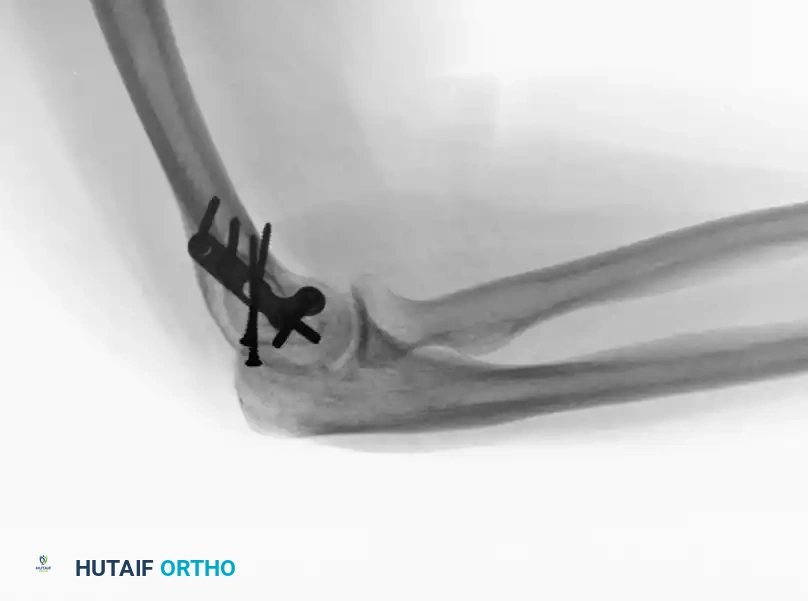

Intraoperative view of plate application through a triceps-reflecting approach, preserving the extensor mechanism.

Radiographic confirmation of bicolumnar fixation achieved via a triceps-reflecting exposure.

These approaches are particularly advantageous when total elbow arthroplasty (TEA) is considered as a backup option, or in patients with severe osteopenia where osteotomy healing is questionable.